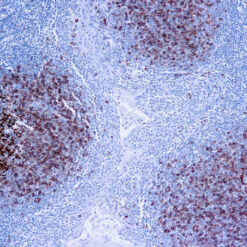

CD79a Antigen (HM47/A9)

This antibody is specific to human CD79a antigen complex, consisting of two polypeptides non-covalently associated with membrane-bound immunoglobulins on B cells. This complex of polypeptide and immunoglobulins constitute the B cell antigen receptor. The two components of this complex are designated CD79a and CD79b. The CD79a antigen appears at the pre-B cell stage, early in maturation and persists until the plasma cell stage. The CD79a antigen is found in majority of acute leukemias of precursor B cell type, in B cell lines and B cell lymphomas.

| Positive Control Tissue | Tonsil |